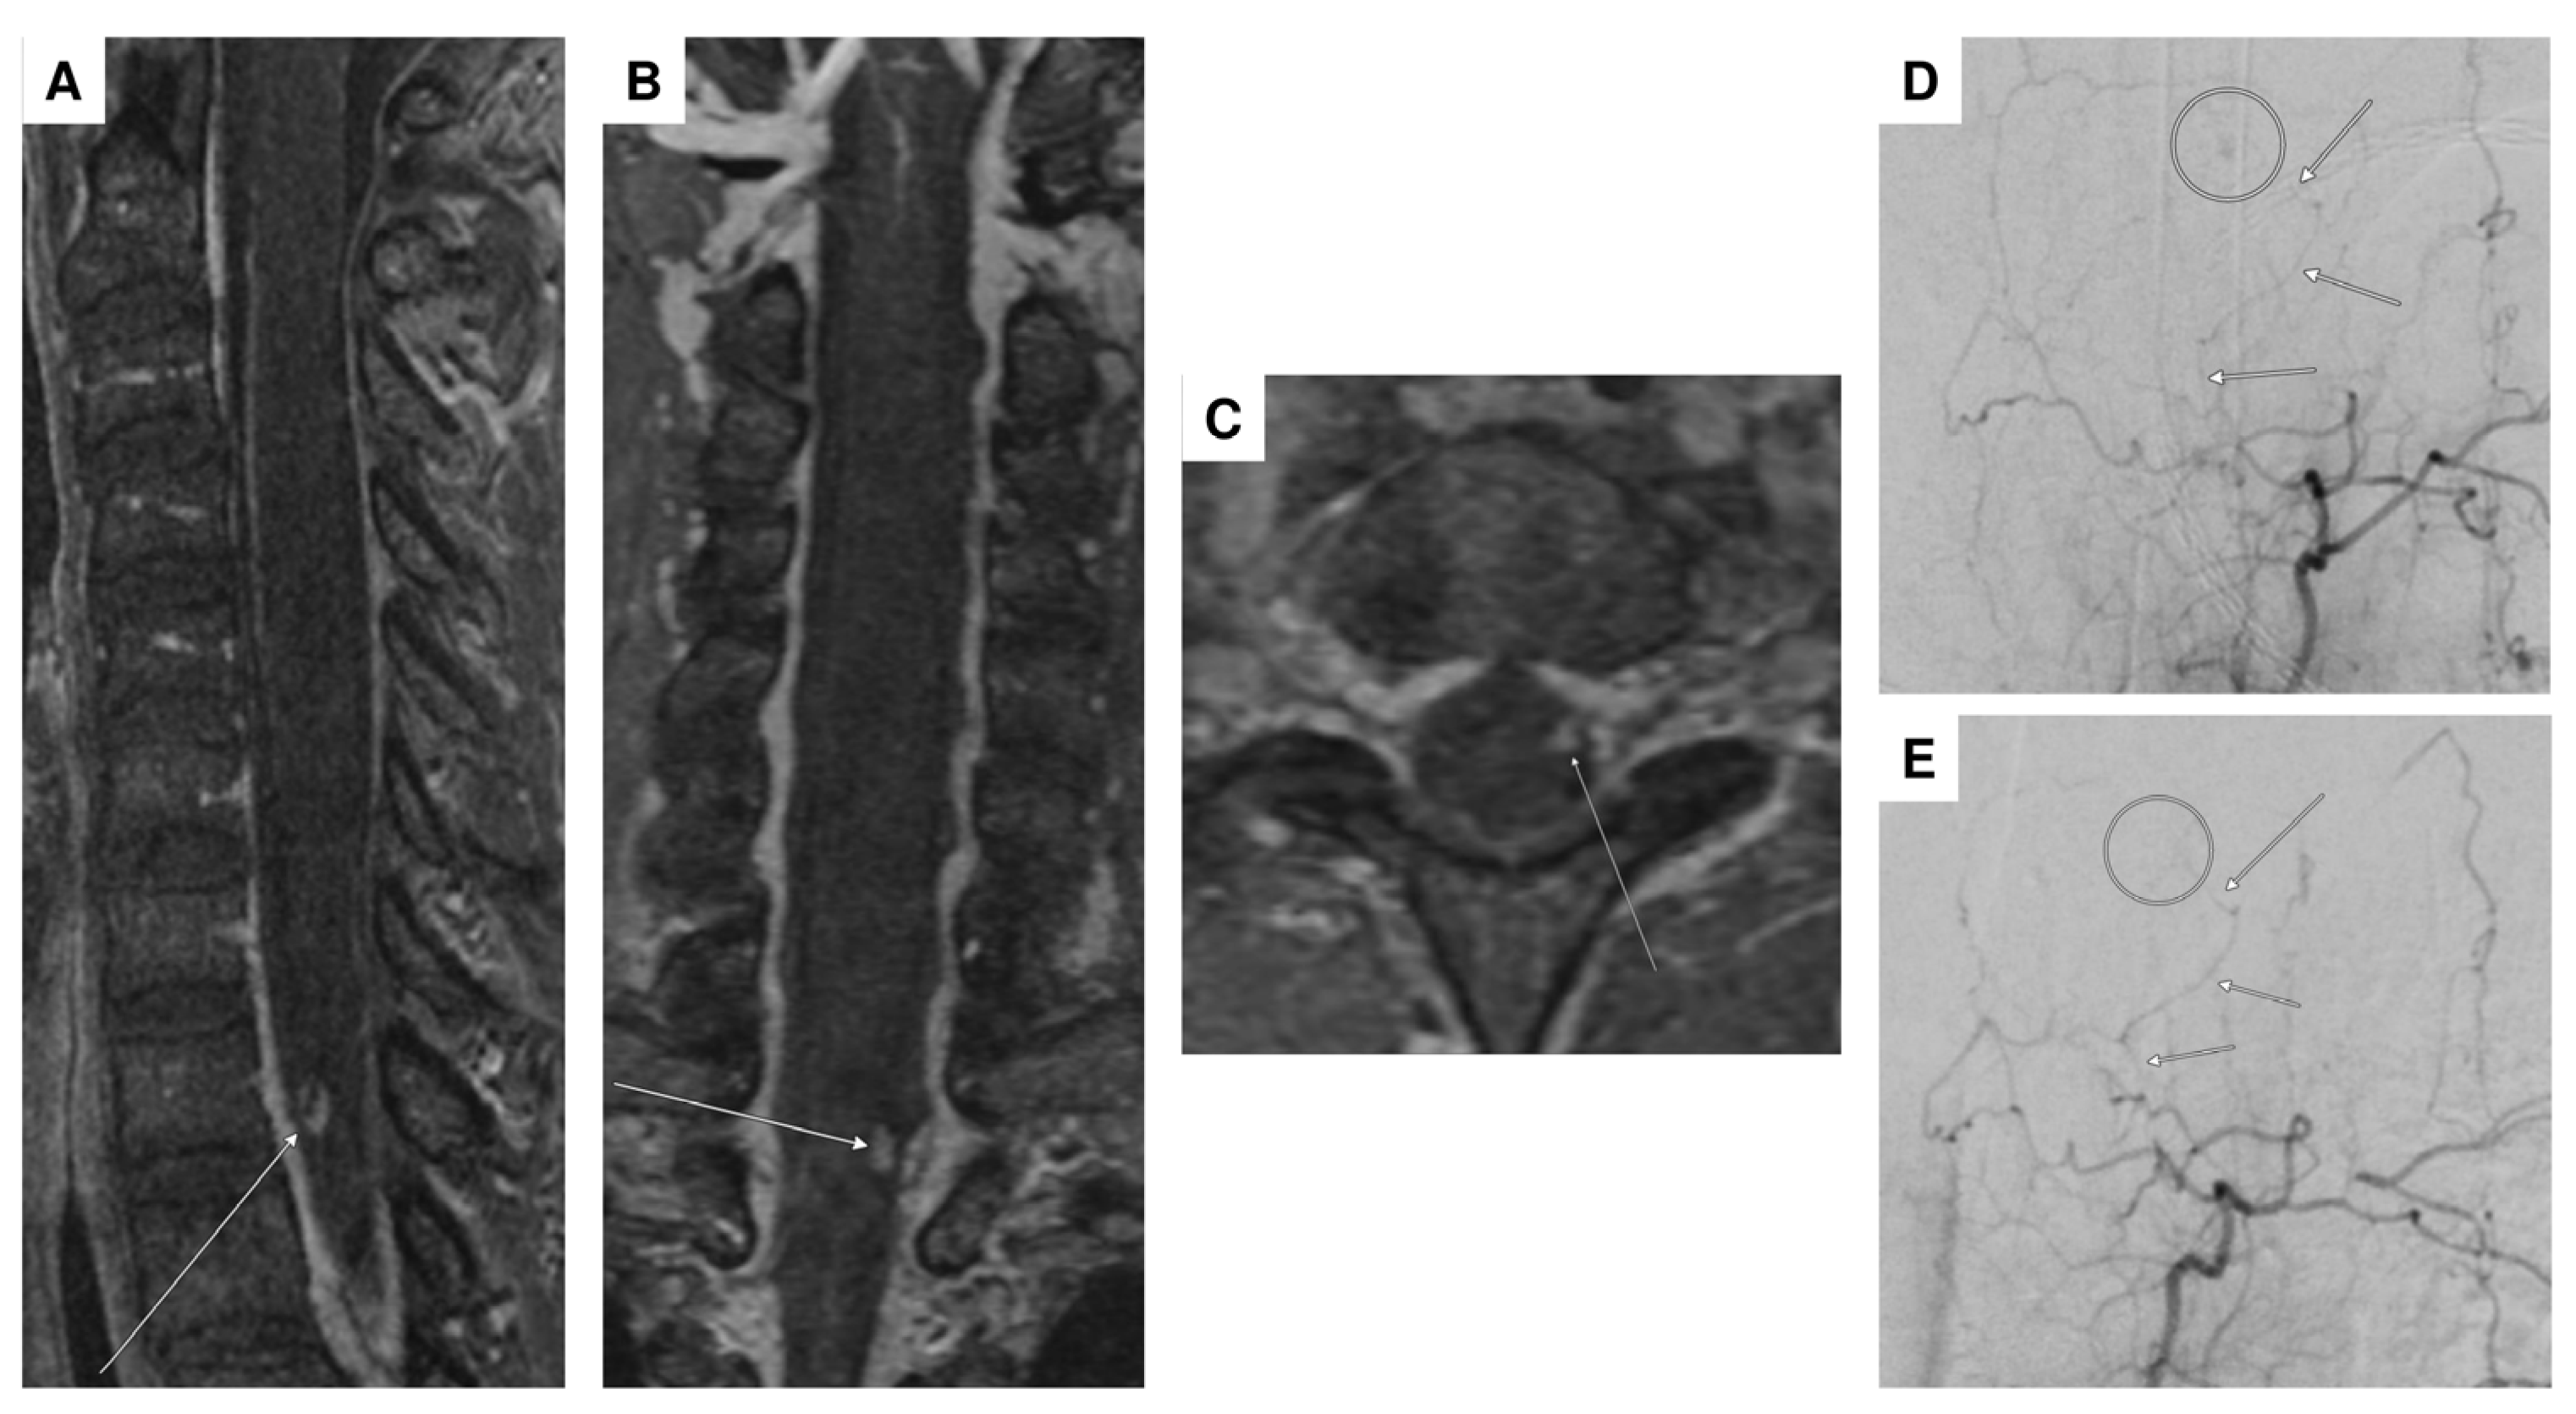

| 1 | F | 47 | headaches and pain in the back/neck pain, nausea, vomiting, photophobia/phonophobia | no focal neurological deficit | SAH Fisher IV with spinal aneurysm at T1 | aneurysm | lumbar puncture, multiple DSA, multiple spinal MRI | conservative |